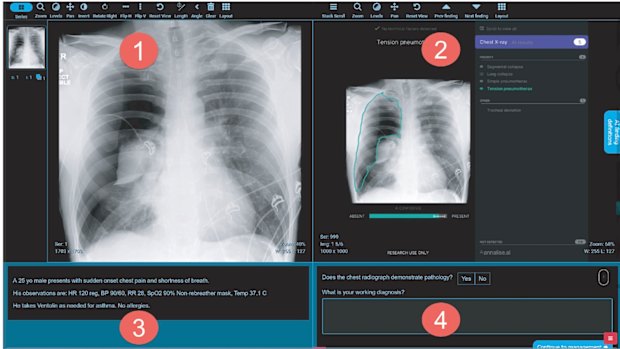

(1) chest X-ray viewer; (2) AI findings viewer; (3) description of the patient’s complaint, symptoms and observations; and (4) a response panel for recording diagnosis.

The slides were divided into four panes: (1) chest X-ray viewer; (2) AI findings viewer; (3) description of the patient’s complaint, symptoms and observations; and (4) a response panel for recording diagnosis.Credit: Emergency Medicine Journal